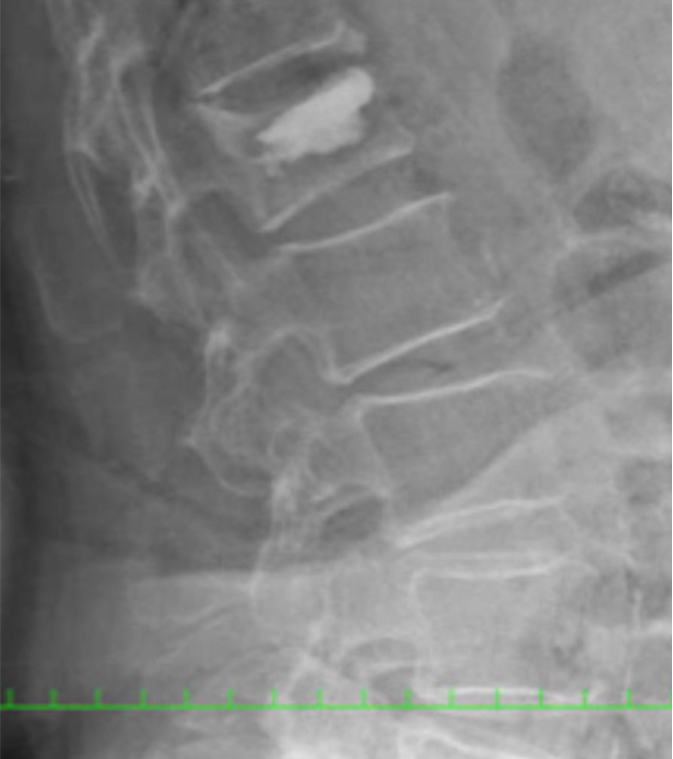

日本,骨質(zhì)疏松癥的人群成為老齡化社會已經(jīng)說是顯著上升到10多萬。伴隨著的是,它也已成為誰在輕微外傷和日常生活的操作經(jīng)歷脊柱壓縮性骨折的病人越多。作為初始治療,休息,口服中藥,緊身胸衣,保守治療,如恢復(fù)完成后,你有良好的臨床效果不能獲得。在另一方面,獲得不夠保守,盡管治效果果,變成了假關(guān)節(jié)(其中骨不完全愈合的狀態(tài)),疼痛也有剩余的情況下。這樣,對于因脊椎骨折剩余的痛苦,我們有各種各樣的手術(shù)。

引起的原發(fā)性骨質(zhì)疏松椎體壓縮性骨折,改編已執(zhí)行積極BKP(由氣球皮椎體成形術(shù)),如果有的話。

在全身麻醉的風(fēng)險案件或案件之外的BKP適應(yīng),具有在局部麻醉下一個PVP(經(jīng)皮穿刺椎體成形術(shù))與我院放射科協(xié)作去協(xié)同放射科。

在比BKP或PVP其他操作,它是融合,并用人造骨經(jīng)皮椎弓根螺釘或HA(羥基磷灰石)椎體成形術(shù)的組合。